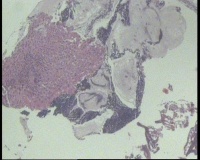

镜下见鳞状上皮大部分如(图1) ,仅局灶鳞状上皮异型(图2-4),细胞似牵拉变形,部分腺腔内见异型细胞团,这些细胞跟LEEP刀手术电凝有关系吗?这个怎么报?累腺明显,上皮图1怎么报?能报CINII—III累及腺体吗?还是宫颈高级别鳞状上皮内病变累及腺体

图2

CIN2-3累腺,有机械损伤,要按1-12点分别报告,要报告内外切缘情况。